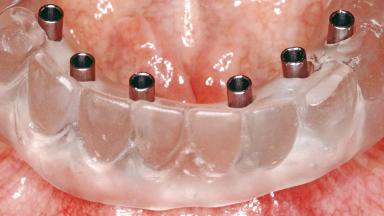

Conventional Loading of Six Implants in the Mandible and Final Restoration with a Full-Arch Metal-Ceramic FDP

A 68-year-old, completely edentulous male patient presented for evaluation and treatment options. He reported excellent general health and was taking no regular medication. He had been edentulous for approximately 12 years, having lost his teeth to periodontal disease and dental caries. The patient’s chief complaint was incompetent function. His secondary concerns included his appearance and the desire for a predictable outcome. He attributed his reduced functional capacity to his lower complete denture, which he described as poor. He was particularly concerned with the denture’s instability and poor fit. In general terms, he was satisfied with the maxillary complete prosthesis. The maxillary prosthesis was characterized by adequate retention, stability, and support, although the fit was considered less than ideal.

# of Implants 6

Type of Implants One-Piece

Prosthesis Type FDP

Loading Protocol Conventional/early

Retention Screw-retained, with 4 or more splinted implants Screw-retained, with 4 or more splinted implants